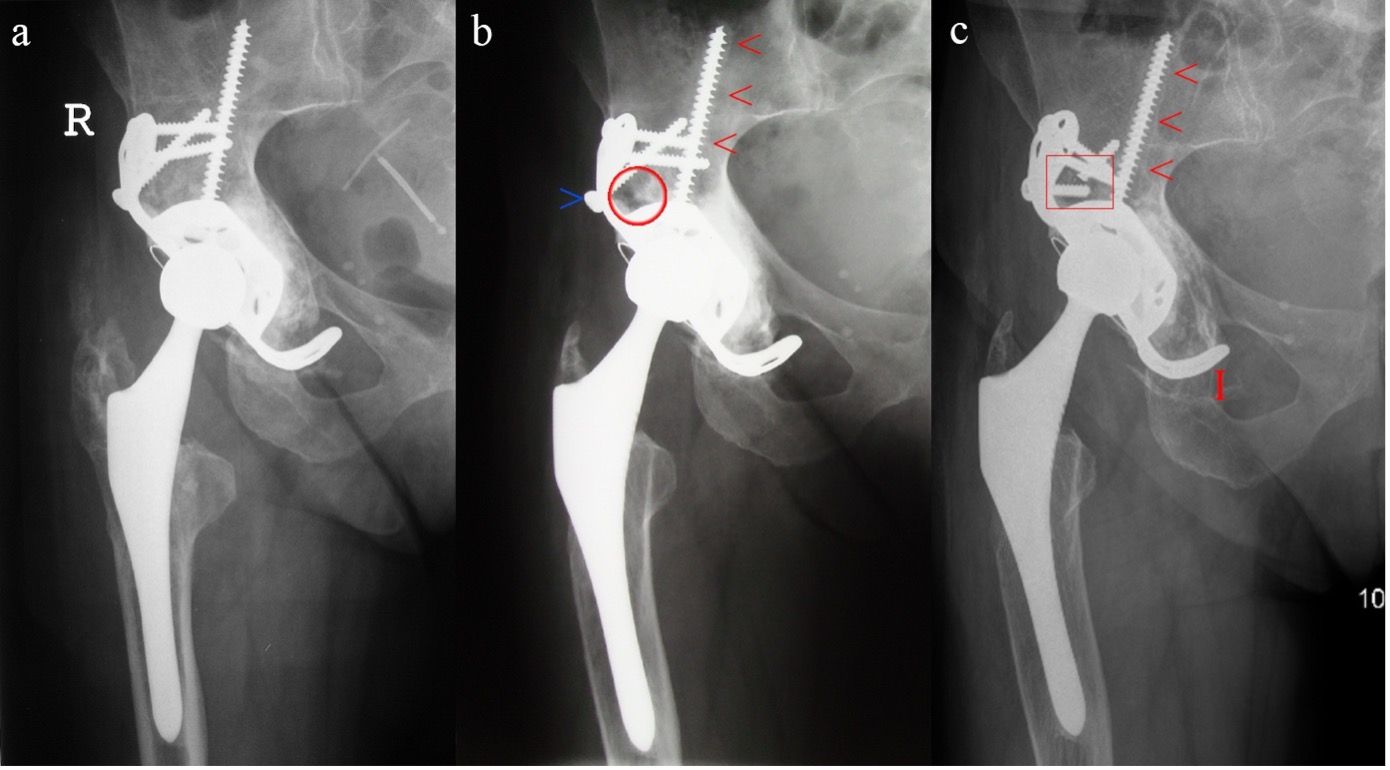

The unenhanced follow-up X-ray images (see Fig. 7) shows good bone fusion of the inserted bone in 2006 at the 4-year interval, with normally positioned acetabular component without evidence of loosening. As early as 2010, at the 8-year interval, osteolysis of the superolateral acetabular teardrop is obvious, with a lysis margin along the acetabular dome screw and visible backtwist of the dynamic hip screw (at-risk implant). The next visit of the patient was only arranged in 2020 with suspected symptomatic loosening of the indwelling acetabular component on the right. The unenhanced X-ray follow-up image confirmed this suspicion and presented with complex findings (see Fig. 7).

In order to clearly identify this defect and to plan the intraoperative procedure, an organized procedure as specified by ADC is the obvious approach. The diagnostic process is illustrated with an example in Figure 8. Figure 9 also shows the involvement of the posterior acetabular column in the CT imaging.

In summary, this shows a high-grade Type 3 C defect. According to the therapeutic ADC algorithm, this requires revision with metallic augmentation in the load-bearing zone of the superolateral and dorsal acetabular rim. Since this is a bony defect of >10 mm, an anatomical ileum tension band should be used for additional stabilization and preventing major relative movements. In our procedure, a modular support cup is used to meet the requirements with a caudal hook and the option of intraoperative adjustment with various augmentations and tension bands [10]. In addition, debrided bone defects should be augmented with biological material using impaction bone grafting outside of the loadbearing areas of the acetabular rim.